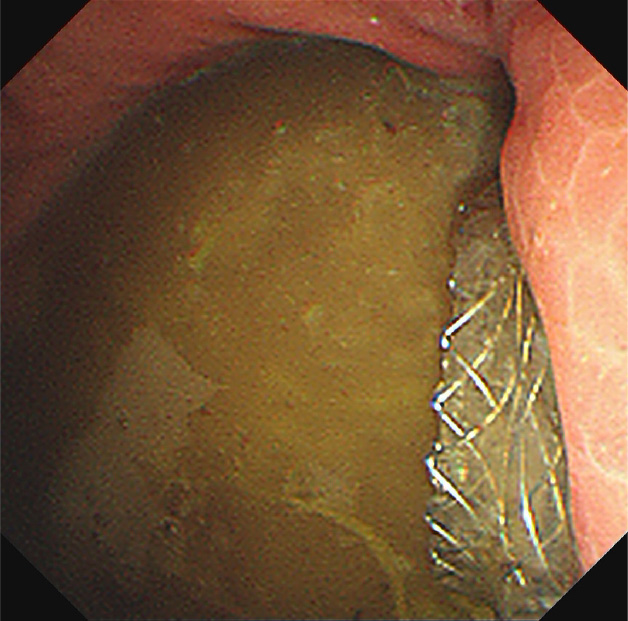

急性胆嚢炎に対するEUS下胆嚢ドレナージ(LAMS留置)